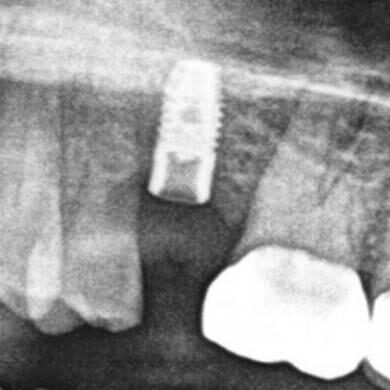

ULTRASONICS: Complications of Abutment Screw Retrieval Secondary to Prior Ultrasonic Attempts

There has been much written on the use of ultrasonics in retrieving fractured screw fragments, which I didn’t think a lot about until May of 2023, as it has not been a part of my fractured screw retrieval algorithm.